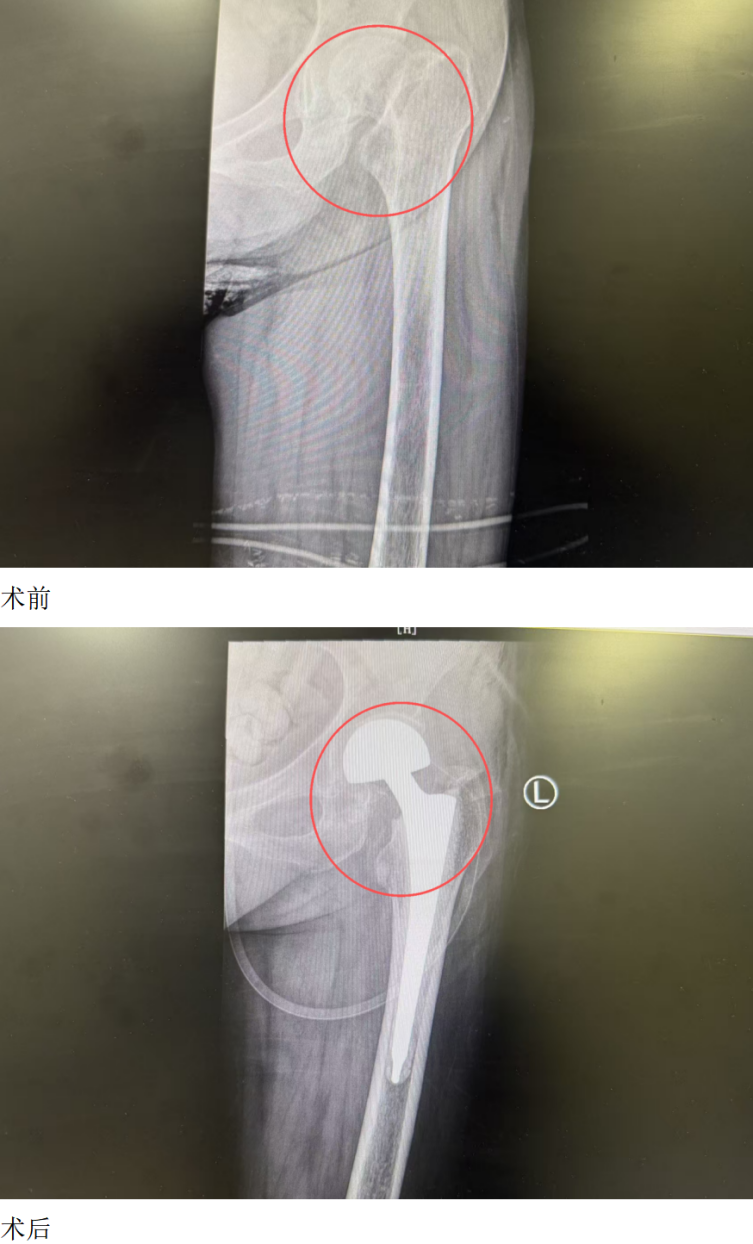

入院检查结果令人揪心。刘奶奶除左侧股骨颈骨折外,还患有重度骨质疏松、2型糖尿病、双侧多发肋骨骨折(右侧3 - 7肋、左侧5 - 7肋)、陈旧性脑梗死、脑萎缩、间质性肺炎及肺结节等多种基础疾病。长期卧床加上糖尿病影响,她的血糖控制不佳,肺功能也较差,给后续治疗带来极大挑战。

针对刘奶奶的复杂病情,骨科一病区团队迅速组织多学科会诊,邀请内分泌科医生介入。通过胰岛素泵精准调控血糖,同时指导刘奶奶进行踝泵训练、股四头肌等长收缩等康复锻炼,为手术筑牢基础。待刘奶奶血糖平稳、身体状况达到手术条件后,由骨科一病区杨鹏主任主刀,顺利为她实施了关节置换手术。

术后第一天,刘奶奶的疼痛症状明显改善,已能在辅助下下地行走,成功规避了长期卧床可能引发的肺部感染、血栓、压疮等风险。